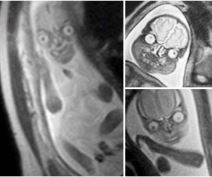

Od pupka neobičnog oblika, preko slike magnetne rezonance bebe u stomaku, stepenica koje ne znamo gde vode (pravo iz kupatila), strašnog zatvora u magli, pa do komaraca na ljudskoj koži i balona u podrumu čoveka koji on tamo nije ostavio, samo su neki od ovih prizora.